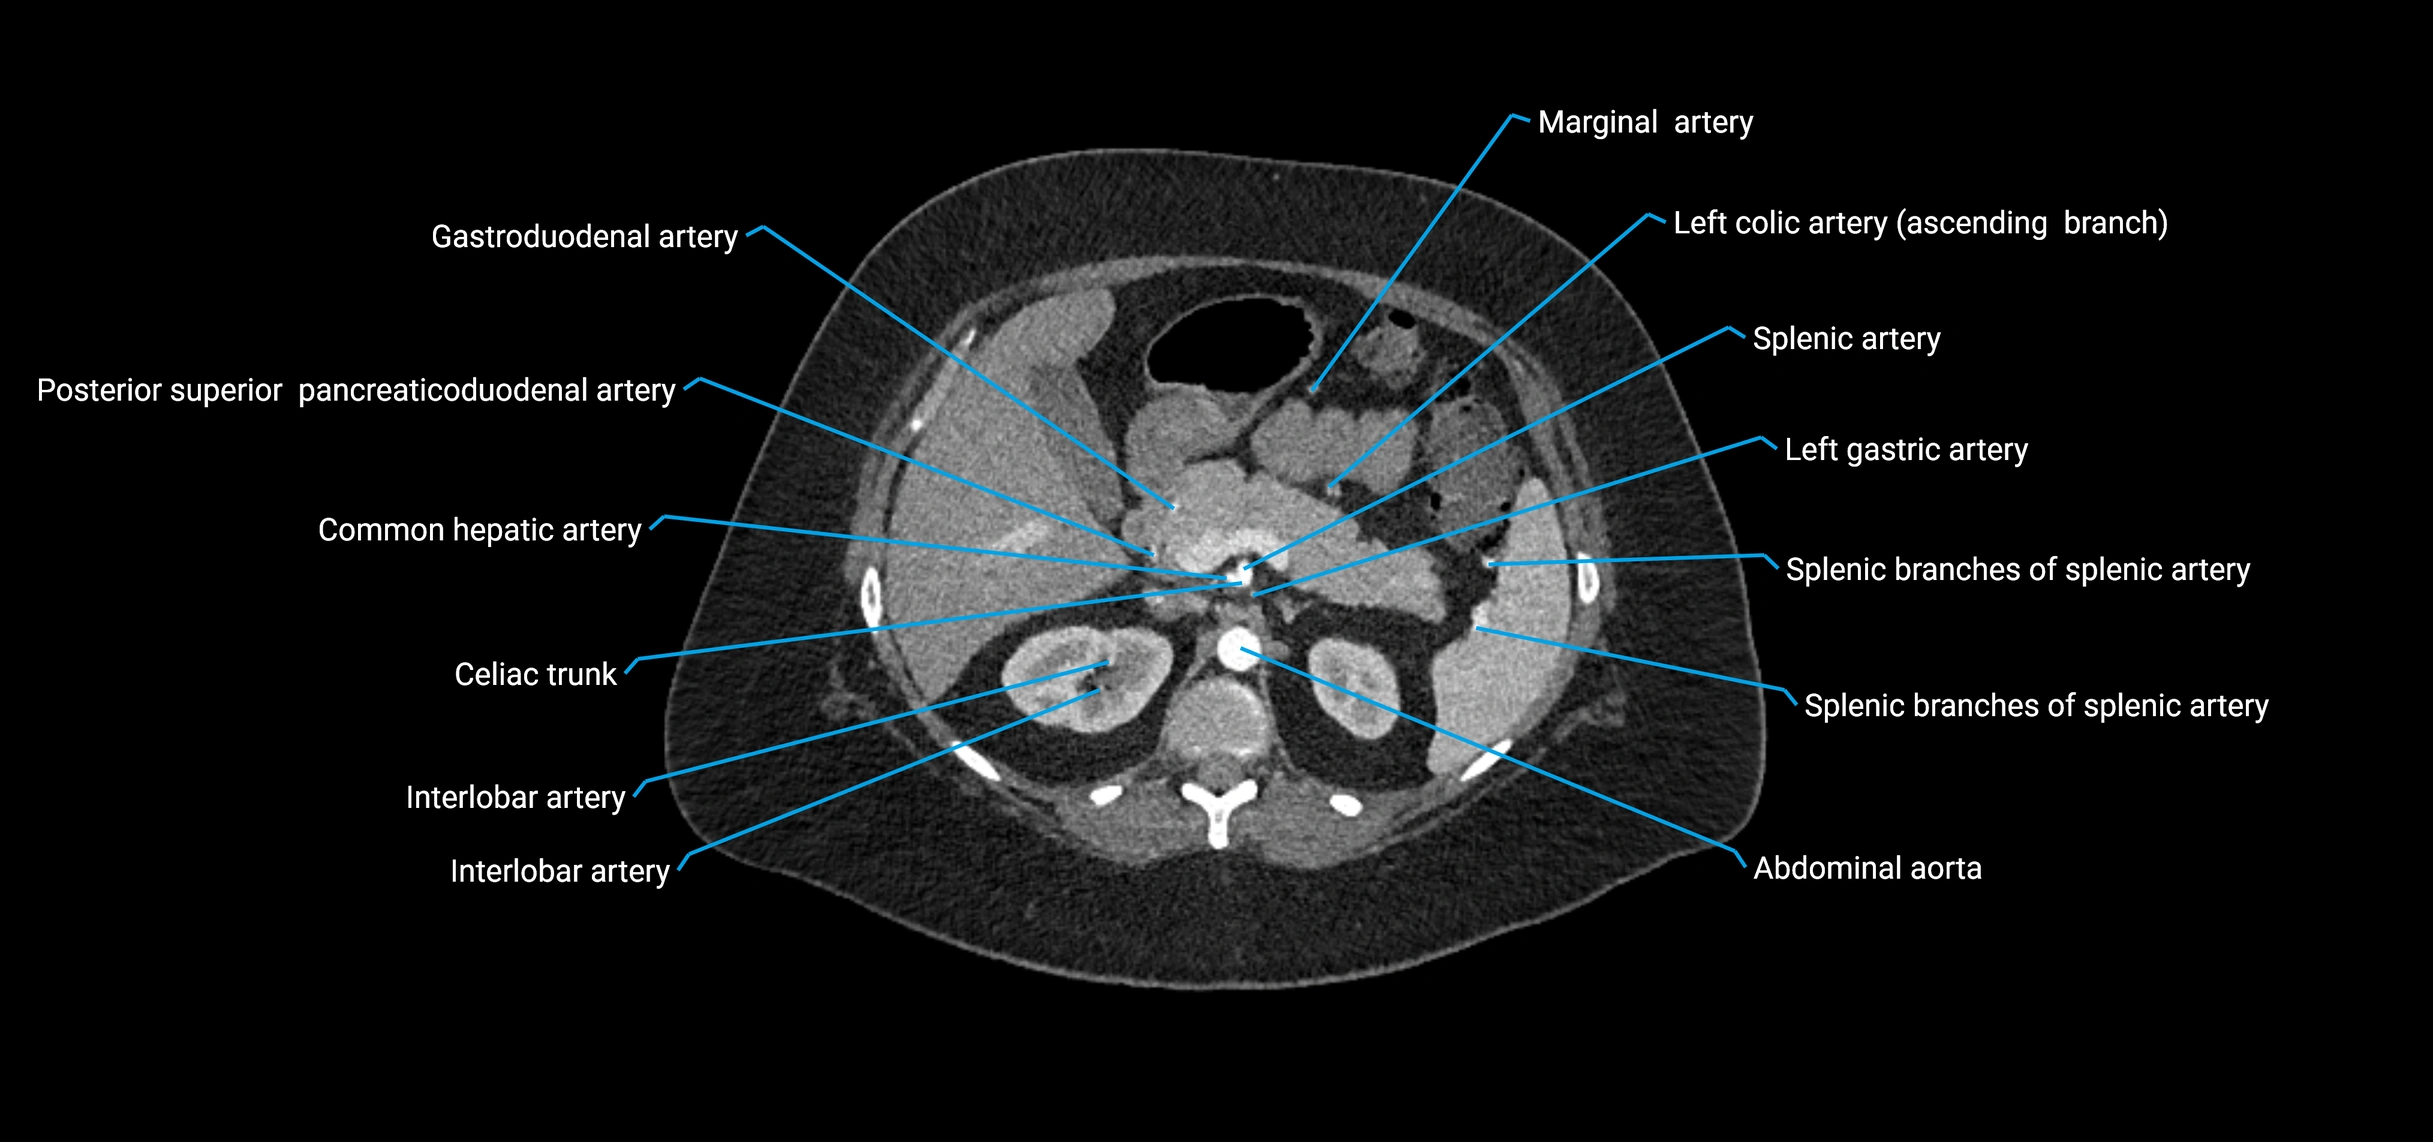

Contrast-enhanced CT (CTA):

• Gold standard for abdominal aortic imaging

• Provides excellent detail of lumen, wall, aneurysm, thrombus, and branch vessels

• Multiplanar and 3D reconstructions help in aneurysm measurement, stent graft planning, and dissection evaluation

• Detects acute rupture, traumatic injury, or occlusion with high sensitivity